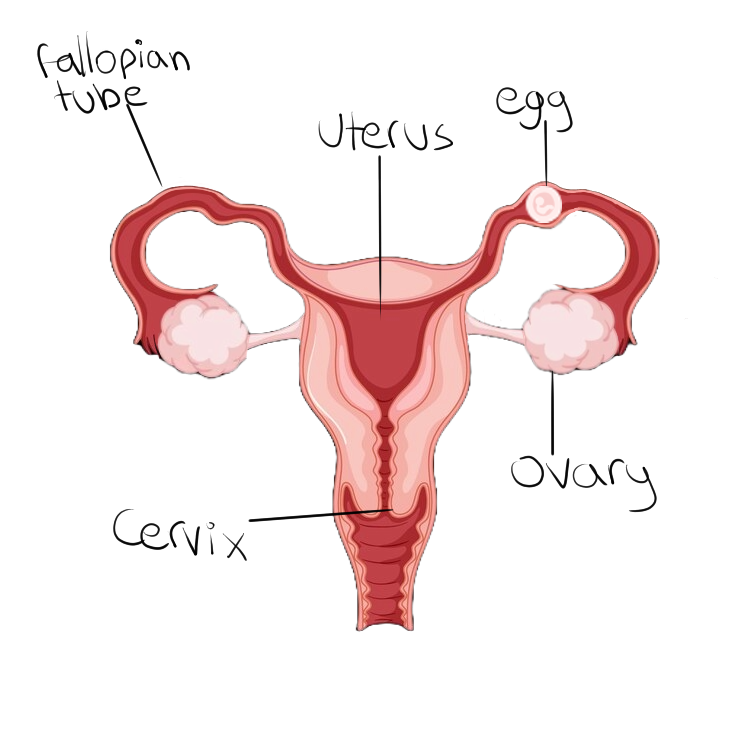

জরায়ুর বাইরে শরীরের কোনও অংশে, সাধারণত ফ্যালোপিয়ান টিউবে, অথবা জরায়ুর গুরুতরভাবে ক্ষতিগ্রস্ত অংশে, জাইগোট যখন নিজেকে রোপণ করে, তখন একটি এক্টোপিক গর্ভাবস্থা ঘটে।

Ectopic pregnancy occurs when the zygote implants itself to a part of the body outside of the uterus, most commonly the fallopian tubes, or in a heavily scarred part of the uterus.